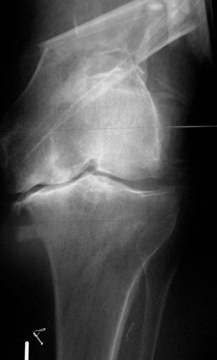

90-jährige Patientin mit distaler Oberschenkel-trümmerfraktur